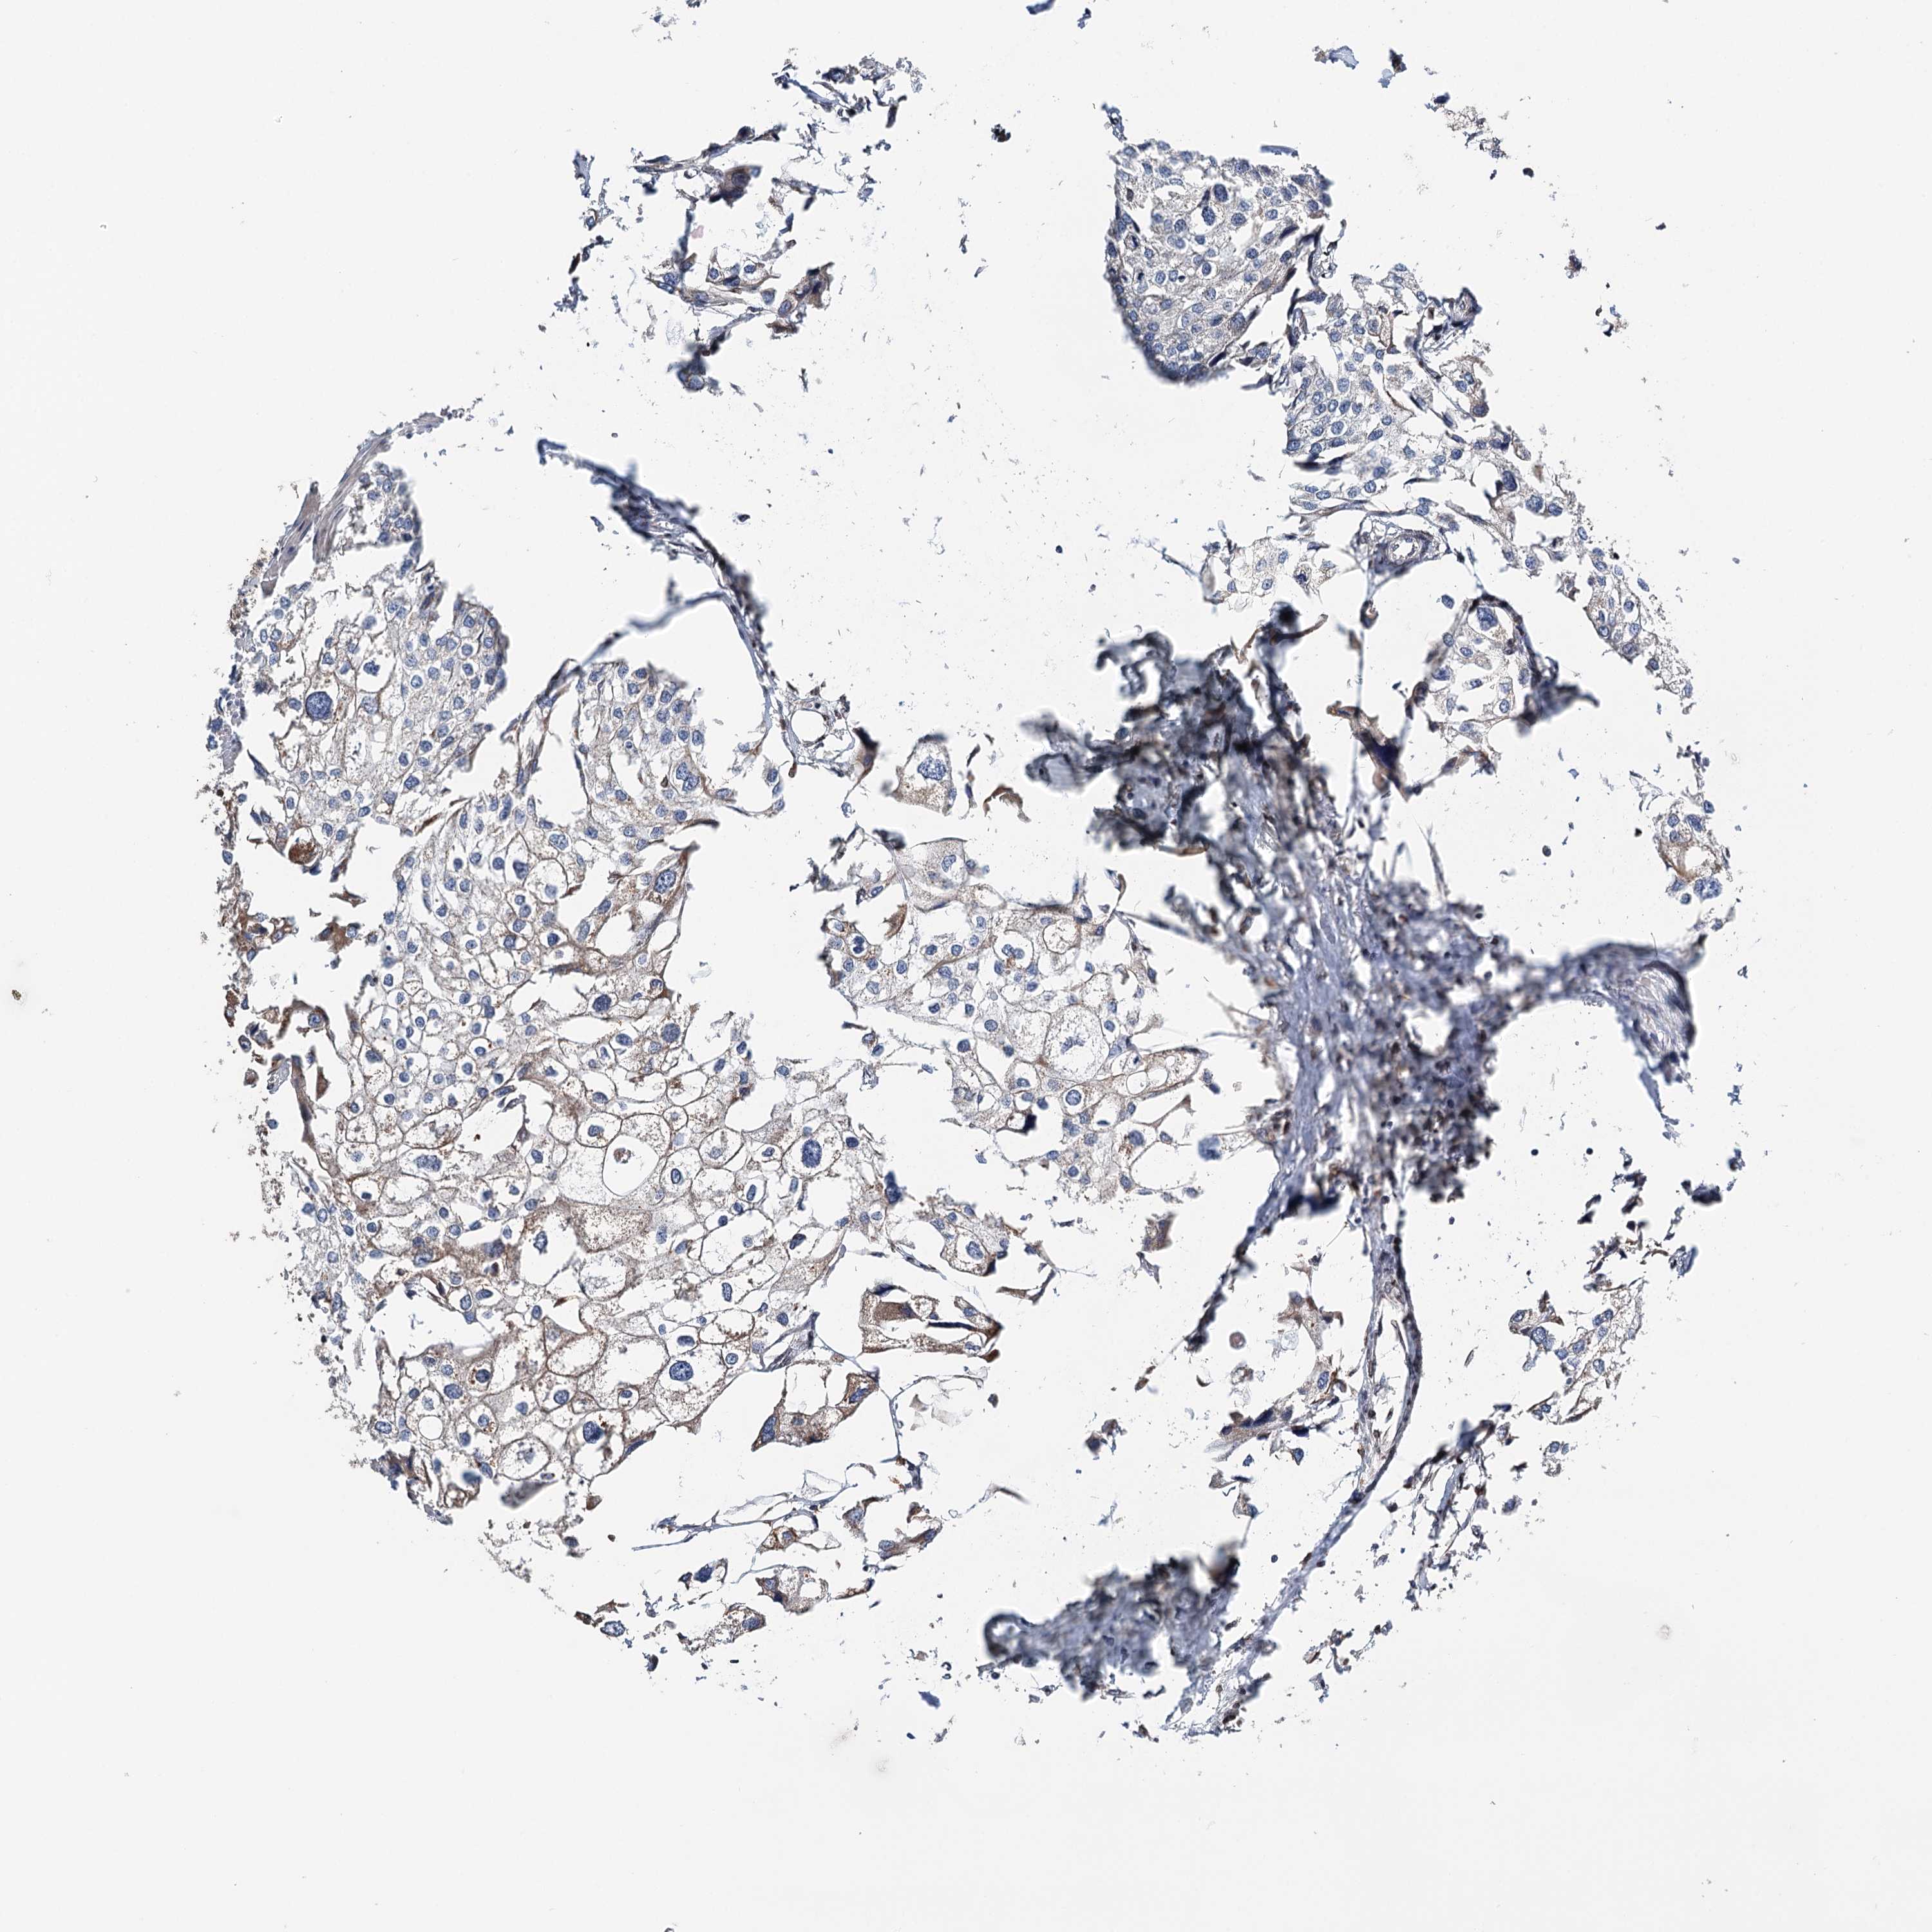

UROTHELIAL CANCER - Protein expressioni

A mouse-over function shows sample information and annotation data. Click on an image to view it in a full screen mode. Samples can be filtered based on level of antibody staining by selecting one or several of the following categories: high, medium, low and not detected. The assay and annotation is described here.

Note that samples used for immunohistochemistry by the Human Protein Atlas do not correspond to samples in the TCGA dataset.

Antibody stainingi

Antibody staining in the annotated cell types in the current human tissue is reported as not detected, low, medium, or high, based on conventional immunohistochemistry profiling in selected tissues. This score is based on the combination of the staining intensity and fraction of stained cells.

Each image is clickable and will lead to virtual microscopy that enables deeper exploration of all samples and also displays staining intensity scores, fraction scores and subcellular localization as well as patient and tissue information for each sample.

Antibody HPA037786

Antibody HPA038034

Antibody HPA038867

Antibody HPA038868

Urothelial carcinoma, High grade

Urothelial carcinoma, Low grade

Urothelial carcinoma, NOS